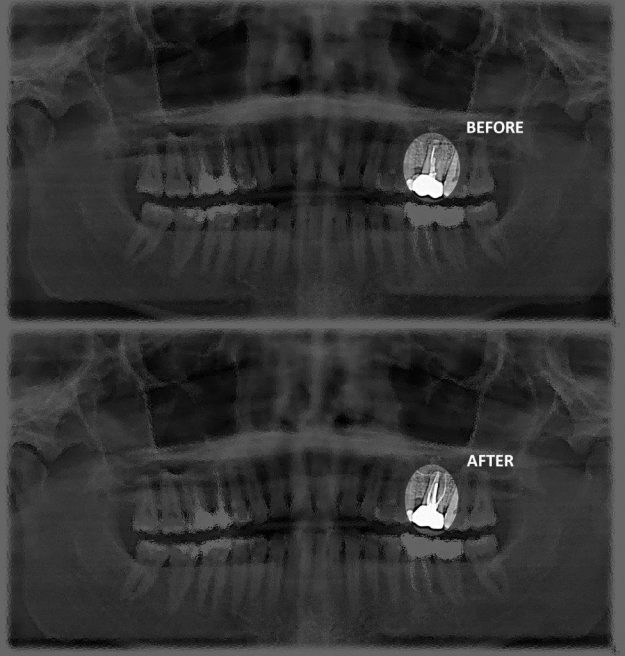

Don’t be in a Hurry to extract a tooth! Dr. Sameti Saves Natural Teeth!

Don’t be in a Hurry to extract a tooth! Dr. Sameti Saves Natural Teeth! Today, it is easier than it has ever been in the past to save a natural tooth and avoid extraction. However, there are many cases where dental care providers across the country will recommend the extraction of a tooth where in…